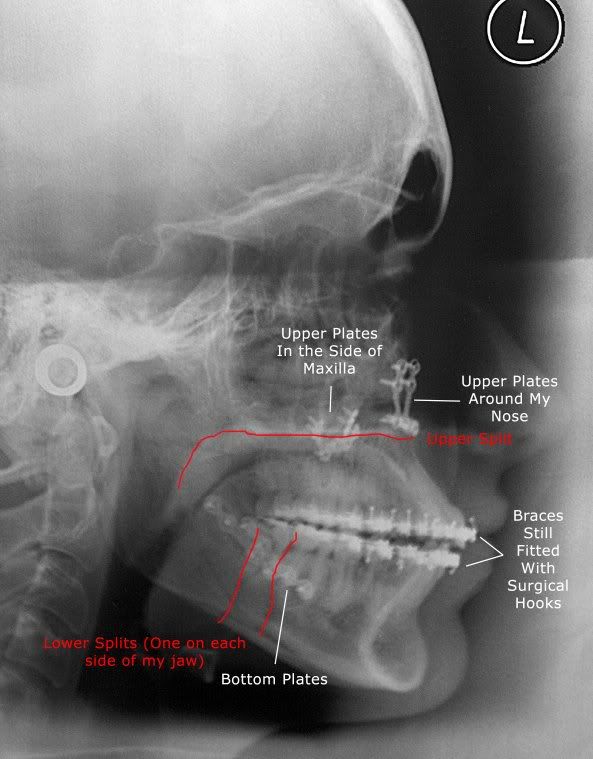

From www.archwired.com

Vibrating Plates When Blowing Your Nose? Metal Mouth Message Board Vibrating Nose a feeling of pulsation in the nose is not a very common symptom, however that in itself is nothing to be alarmed about. you may have a crust lodged in your nose after your surgery, which is normal if irritating, but should come out on. A doctor has provided 1 answer. Having a nasally voice may impact your. Vibrating Nose.